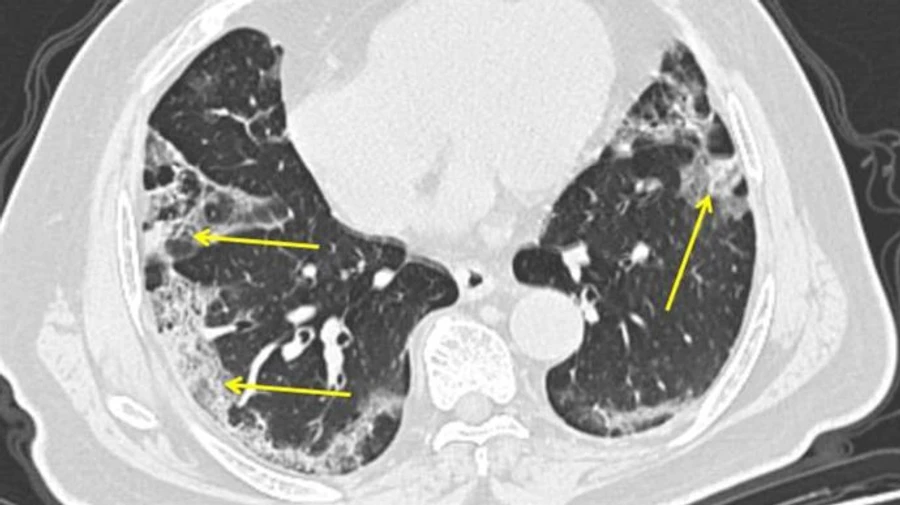

За тиждень МОЗ зафіксувало 22,4 тисячі пневмоній

За тиждень із 5 до 11 жовтня в Україні діагностували 22,4 тисячі пневмоній, з середини липня цей показник зріс у 5 разів.